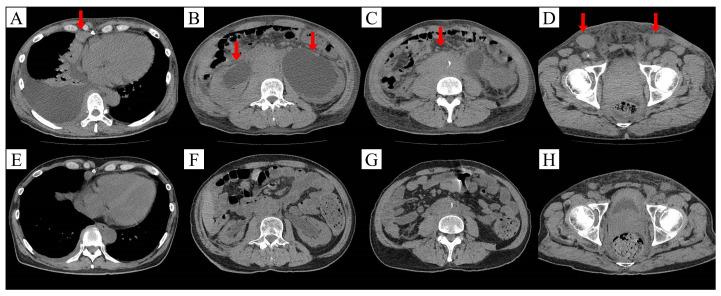

High-grade B-cell lymphoma with MYC and BCL2 and/or BCL6 rearrangements, also known as double-hit lymphoma, has been reported as refractory to R-CHOP therapy and requires more intensive regimens. However, intensive and safe regimens for patients with renal dysfunction are unknown. Herein, we report the successful use of DA-EPOCH-R therapy for double-hit lymphoma in a 64-year-old man with renal dysfunction. The patient had lymphoma-induced bilateral ureteral obstruction. Although renal dysfunction remained after removing the obstruction using R-CHOP therapy, we completed six cycles of DA-EPOCH-R therapy without any major adverse events. DA-EPOCH-R therapy may be a safe regimen for renal dysfunction patients.